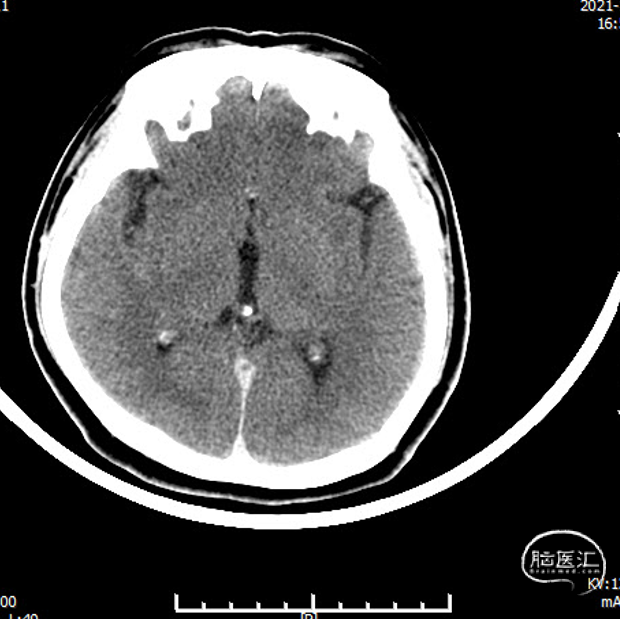

脑血管造影:右侧大脑中动脉M1段局部瘤样突起,远端重度狭窄,考虑右侧大脑中动脉M1段夹层动脉瘤。

治疗之前3D和工作位(测量病变处近远端血管管径,M1近端1.9mm,M1远端1.7mm)。

全麻下,通过同轴技术泥鳅导丝、5F VTK将6F长鞘置于右侧颈总动脉,撤出微导丝及VTK,随后路图下泥鳅导丝携6F Tethys®中间导引导管置于右侧颈内动脉C4段。撤出泥鳅导丝,在6F Tethys®中间导引导管路图下,顺导丝(交换导丝)将加奇SacSpeed® 1.75×12mm球囊置于狭窄段,路图下精确定位,以1atm/30s速度缓慢扩张球囊至6atm左右,释放球囊压力。造影提示右侧大脑中动脉狭窄明显改善,瘤样突起减少,撤出球囊。

支架植入后造影及3D。

术后即刻复查头颅CT未见异常。